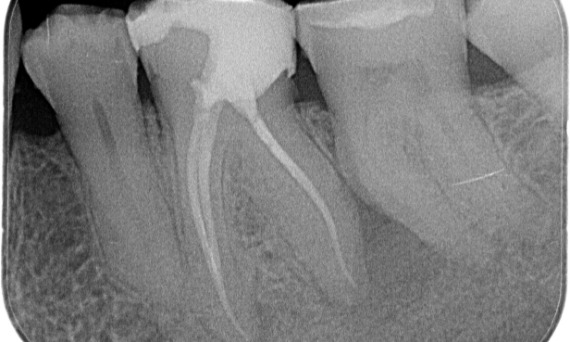

"Ein patienten- und behandlungsorientierter Erfolg." Dr. Cowie

Vorher: Periapikale Radioluzenz primär an der distalen Wurzel und Verlust der Lamina dura an der mesialen Wurzel.

Nachher: In diesem Fall wurde TruNatomy gewählt, um einen kariesfreien Ansatz zu ermöglichen und sich auf den Erhalt des perizervikalen Dentins zu konzentrieren, insbesondere auf der mesialen Seite, wo der Zahn eine minimalere Restauration aufwies.

Bath, UK